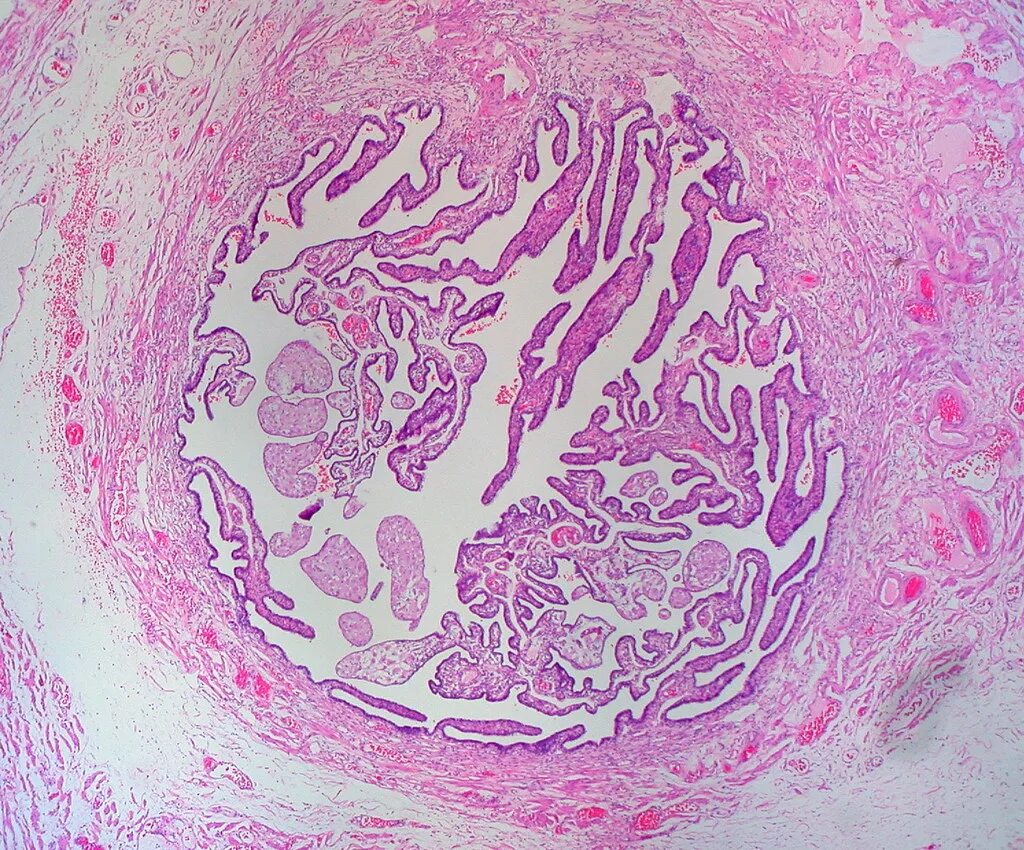

Маточная труба гистология